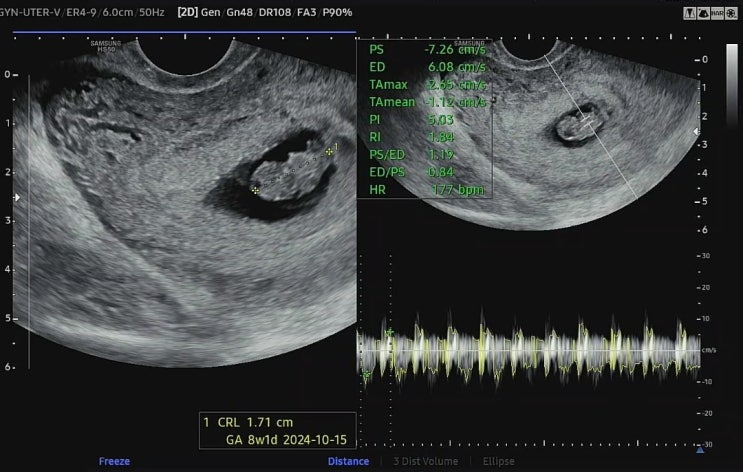

[임신일기] 7~8주차 기록 - 임밍아웃2/난임 병원 졸업

# 7~8주차 기록 임밍아웃2/난임병원 졸업 2024년 3월 9일, 토요일 7주 0일 임밍아웃2 양가에는 임신 하자마...

[시험관 기록] 임신 7주 6일 초음파, 입덧지옥, 임밍아웃

또 일주일이 흘러 임신 7주6일 병원방문 저번주 아기크기가 주수보다 하루 작음 이슈로 걱정이 많은 일주일...